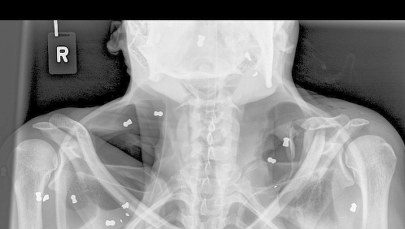

Ranny mężczyzna trafił do szpitala, ma siedem ran postrzałowych, także w okolicy oka. W niektórych ranach znajdowały się jeszcze śruty. W chwili zdarzenia 8-letni syn mężczyzny stał kilka metrów za tatą i znajdował się na linii strzału. Na szczęście nic mu się nie stało - dodała komisarz Pydych.